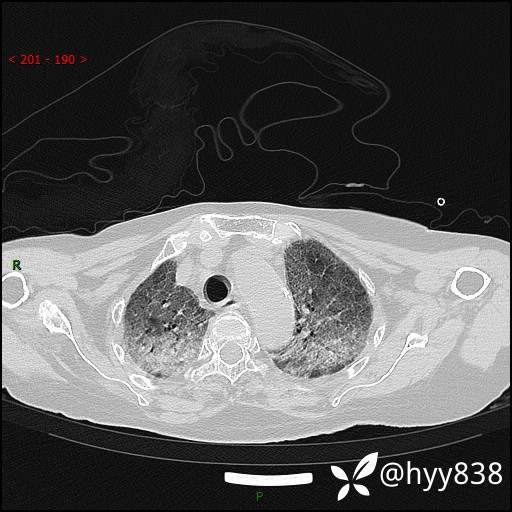

弥漫性肺部病变,辗转当地多家医院未能确诊,拟诊“重症肺炎”入我院--结果公布

患者年龄:69岁

简要病史: 患者20余天前无明显诱因出现发热,最高体温37.5℃,伴头晕,乏力,纳差等不适,无鼻塞,流涕,无咳嗽咳痰,无呼吸困难,无恶心呕吐、关节疼痛等不适,于当地市多家医院就诊,未明确病因,2023.6.23于当地第二人民医院就诊,完善胸部CT示病毒性肺炎,予以抗感染、清热解毒后症状较前稍好转,2天前患者无明显诱因出现活动后喘息加重,伴肌肉酸痛,口干,无明显咳嗽咳痰,今日体温38.1℃,为求进一步诊治来我院就诊,门诊以“ 重症肺炎 I型呼吸衰竭”收入院。 患者起病以来,精神、睡眠、饮食欠佳,大小便正常,体力下降,体重无明显改变。

辅助检查:CT

临床诊断:重症肺炎

胸部CT薄层扫描